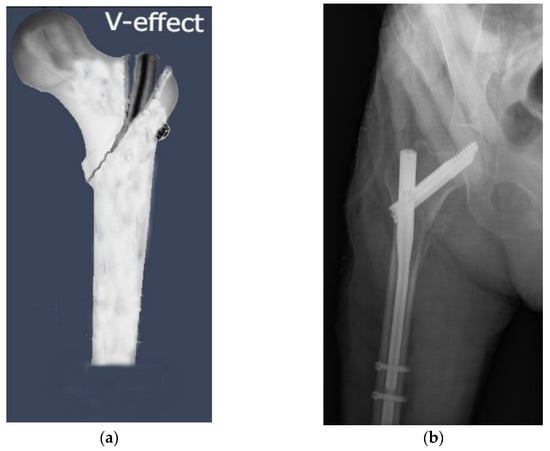

When the fracture line extends all the way to the greater trochanteric tip, an iatrogenic complication known as the ‘‘V-effect’’ might occur following fixation with PFN in IFFs (Figure 2). Hu et al. [40] were the first to provide a detailed description of the V-effect in the academic literature. The V-effect might be regarded as the result of two mechanisms. The first component is the placement of the guide wire to the fracture line, which continues towards the trochanteric point, instead of the guide wire’s point of entry in accordance with the PFN model. Second, since the guide wire penetrates the intramedullary area in the incorrect way, the drilling performed on it produces a hinge impact rather than an intramedullary hole for PFN [41]. The varus of the femoral neck with respect to the femoral shaft seems to be a direct result of the V-effect. This is related to a large extent to the fact that PFN generates separation in the fracture zone, which eventually reaches the apex of the great trochanter. Based on the results of the current study, 9.7% of participants experienced the V-effect. This was consistent with the 9.4% incidence of the V-effect reported by Eceviz et al. [41] in their 2021 study. They also discovered that InterTAN nails had the lowest occurrence of the V-effect compared to PROFIN nails. Consistent with the previous research, the present study found that the V-effect was most prevalent in the A-PFN group and least prevalent in the InterTAN group. As the second most common complication in the current study, the V-effect was found in 32.9% of 31A2-type fractures but in none of the 31A3-type fractures, leading us to conclude that surgeons should be careful when operating on 31A2-type fractures. Hu et al. [40] advised having an assistant hold the greater trochanter while the surgeon performs reaming at a high rotational speed. Consequently, the proximal femur may have to be widened so that the PFN may be implanted at a more advantageous angle. It was concluded that the V-effect, which contributes to hip varus deformity and non-union, was avoidable. There is a lack of data about the clinical outcomes of patients diagnosed with the V-effect. Several individuals having perfect images did not recover to their former well-being level, while other individuals with the V-effect on images had no noticeable symptoms. Not all of our patients with the V-effect had varus collapse. Clinical results may be affected by the V-effect; hence, further long-term follow-up clinical studies evaluating varus progression in patients with the V-effect and examining this phenomenon are needed.

Figure 2. The ‘’V-effect’’, an iatrogenic complication of proximal femoral nail fixation in intertrochanteric femoral fractures, may develop when the fracture line extends all the way to the greater trochanteric tip. (a) An illustration of the “V-effect”. (b) Observation of the V-effect in a patient who underwent surgery with A-PFN nail.